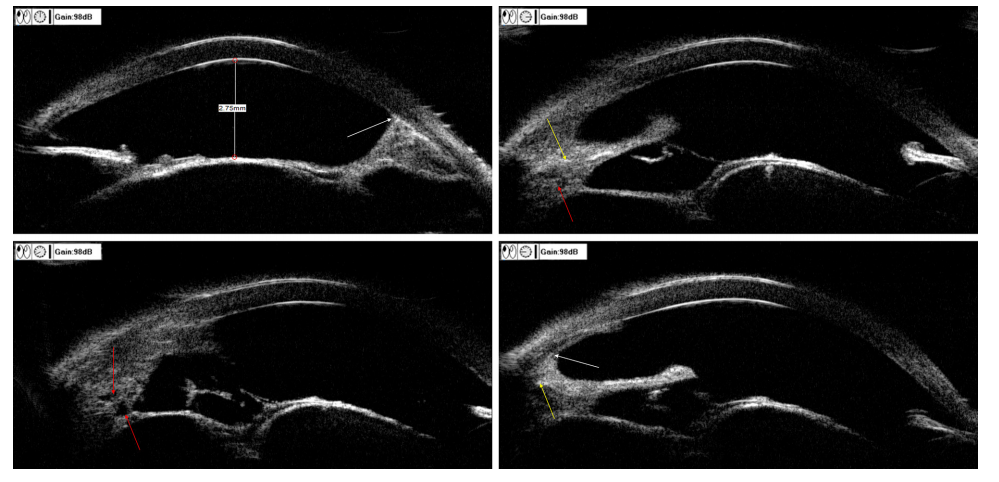

20230601151836_1238.png

图6 术后UBM图像

Figure 6 Postoperative UBM image

6~12点虹膜、睫状体组织结构紊乱,内部可见大小不一的囊腔(红色箭头)及中等反射(黄色箭头),部分与角膜粘连(白色箭头)。

The tissue structure of the iris and ciliary body is disordered at 6–12 o’clock, difffferent sizes of cysts (red arrows) and moderate reflections (yellow arrows) can be seen inside, and some of them adhere to the cornea (white arrows).

患者术后14个月(2020年9月)复诊时右眼视力指数/10 cm ,眼压21 mmHg(局部使用布林佐胺噻吗洛尔) 。检查见颞侧角膜带状变性,中央前房深4角膜厚度,颞下方虹膜缺损,颞侧周边虹膜前粘连,瞳孔散大不规则,晶状体前囊见色素沉积(图5 ) ,眼底视网膜平伏,未见肿物。UBM提示6~12点虹膜、睫状体组织结构紊乱,内部可见大小不一的囊腔,部分呈中等反射并与角膜粘连(图6 )。B超检查未见明显异常。